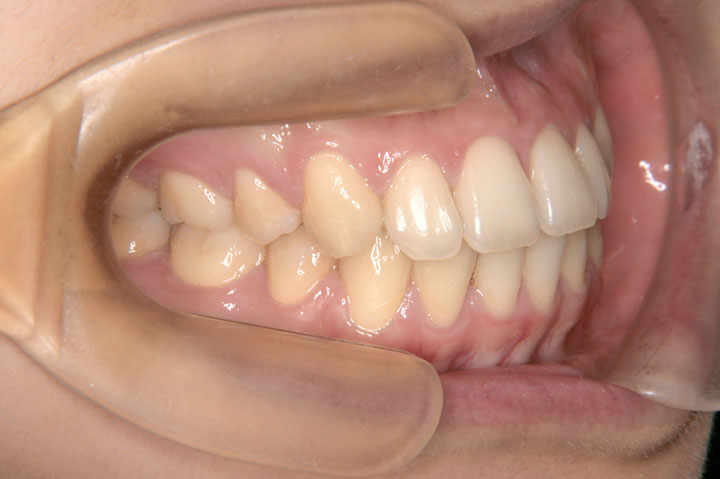

上下顎前突(口元の突出)

叢生(乱ぐい歯)

歯並びを気にして来院された高校3年生の女子です。歯のデコボコとともに口元の突出感を改善するために、上下顎小臼歯抜歯で配列いたしました。上顎は裏側からの矯正装置(ハーフリンガル)を使用し、その後、保定に移行しております。